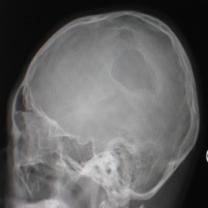

头颅正侧位片:可见右顶部颅骨缺损区,局部软组织隆起,类长圆形,缺损边缘不规则、骨质密度增高合并骨质破坏密度减低,隆起如火山口状(图1)。

图1:(1)正位相见右顶部骨质缺损,局部软组织隆起,边缘不规则,骨质密度增高合并骨质破坏密度减低,隆起如火山口状;(2)侧位相见颅骨缺损区,类似长圆形,缺损边缘不规则